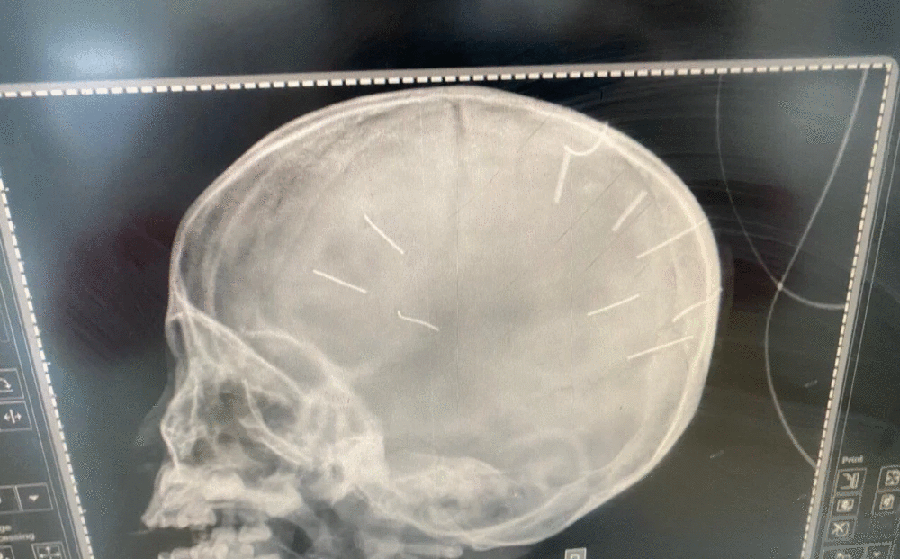

Cháu A được mẹ đưa tới Bệnh viện Đa khoa huyện Thạch Thất hôm 17-1, sau đó được chuyển lên Bệnh viện Saint Paul Hà Nội, trong tình trạng hôn mê sâu, nghi viêm màng não. Chụp hình cản quang thấy nhiều vật thể lạ hình đinh ghim.